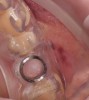

After the surgical stent was tried in and verified (Figure 5), a 5-mm tissue punch was introduced through the surgical stent to remove a core of soft tissue where the implant would be placed. Osteotomy drills matching the implant system to be used were introduced through the surgical stent and taken to the final diameter. The stent limited the depth to 2-mm short of the sinus floor. The stent was removed, the final drill was reinserted into the osteotomy, and a periapical radiograph was taken to verify the depth and orientation to the sinus floor (Figure 6). Next, a 5-mm wide, cupped-end sinus osteotome was introduced into the osteotomy, and another periapical radiograph was taken to check the depth of the osteotomy in relation to the sinus floor. Using a surgical mallet, the osteotome was advanced an additional 4 mm with gentle tapping to elevate the sinus floor atraumatically (Figure 7). A blunt instrument was used to verify the integrity of the sinus membrane and confirm that perforation had not occurred during the sinus lift. Following verification of sinus integrity, the previously created A-PRF+ plugs (Figure 8) were removed from the PRF box and individually placed into the osteotomy (Figure 9). The 5-mm osteotome was used to efficiently press the plug into the osteotomy, filling the space created between the sinus floor and the sinus membrane (Figure 10). The 5.2 x 10 mm implant with fixture mount attached was picked up with the handpiece driver on a surgical handpiece (Figure 11). The implant was inserted with the handpiece using 20 rpms until an insertion torque of 40 Ncm was reached. Final seating of the implant was accomplished with a torque wrench, which was used until the implant was positioned at the correct depth in relation to the site's crestal bone and the cementoenamel junction of the adjacent teeth (Figure 12). The fixture mount was removed, a cover screw was placed into the implant, and a periapical radiograph was taken to verify placement (Figure 13). Because the A-PRF+ is radiolucent when initially placed, its position cannot be ascertained radiographically at the time of surgery. The patient was scheduled for a 1-week postoperative check, at which time the cover screw was visible with slight irritation of the gingiva around its periphery. At the 3-week postoperative examination, the cover screw remained exposed, but the peripheral gingival inflammation was absent and the tissue appeared normal in color and tone.